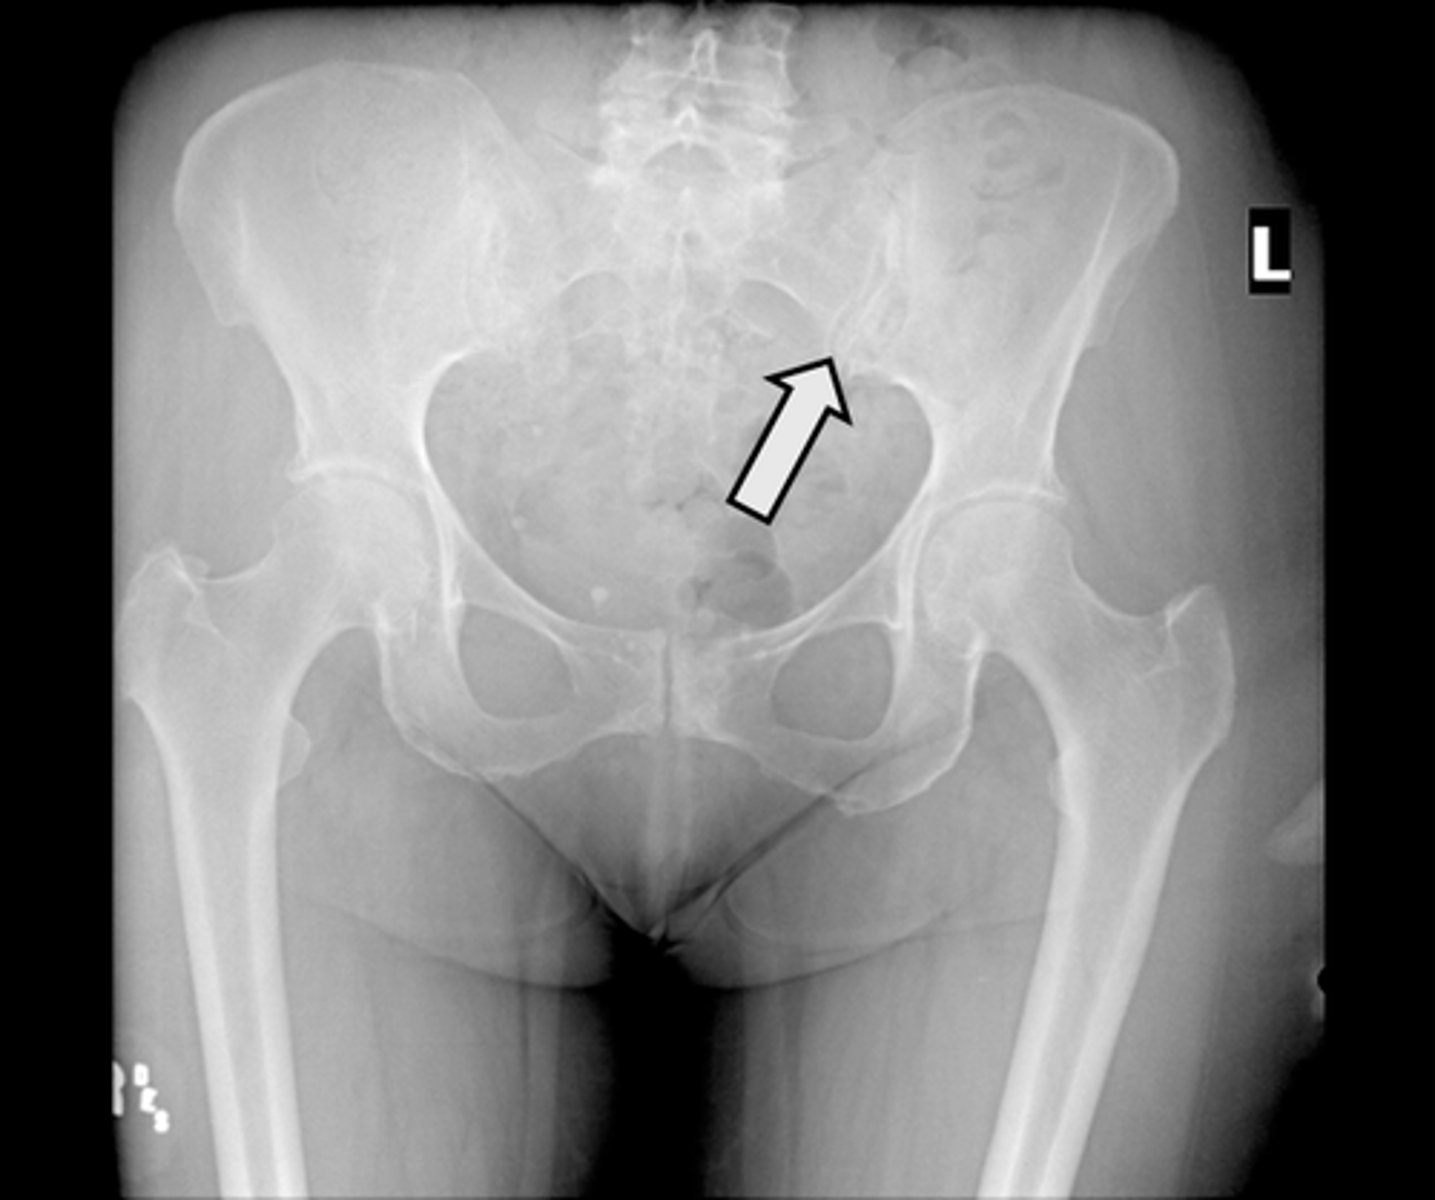

AP pelvis

What is the image?

Acetabulum

What is indicated in the image?

Body of L4

Epiphysial plate

Femoral head

Hip joint

Ilium

Ischial spine

Ischial tuberosity

Nonfused greater trochanter

Obturator foramen

Pubic symphysis

Sacroiliac joint

Sacrum